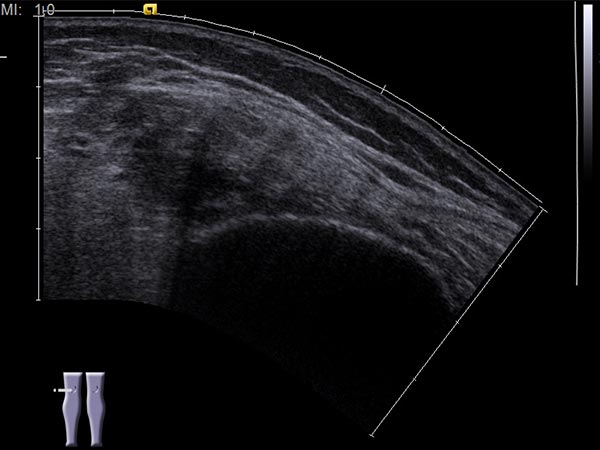

Ultrasound image (automatically assembled 2D image) after sclerotherapy. The hypoechoic cavities of the venous malformation are now occluded by the inflammation induced by sclerotherapy. The image now appears more homogeneous and echogenic on ultrasound. After occlusion of the cavities, painful thrombophlebitis can no longer occur.

Intramuscular venous malformations (VM) are often located in the distal thigh, near the periosteum of the femur. Symptomatology of recurrent pain with accompanying induration leads to imaging, and MRI confirms the diagnosis. During sclerotherapy, it is important to exclude draining or communicating veins of the venous malformation into the deep conducting venous system, as thromboembolic processes can occur via the communicating veins either spontaneously or induced by the therapy. Sclerotherapy occludes the initially open cavities of the VM, which thus becomes more echogenic in ultrasound. Today, the patient is asymptomatic even 2 years and 4 months after the therapy.